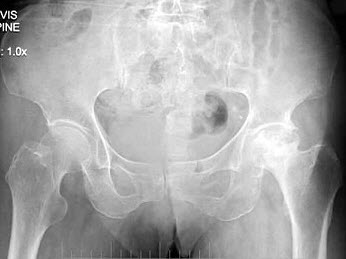

C.患骨增粗,但无骨膜反应

100、单项选择题

患者女,6岁,左下肢跛行三年,直立时臀部后耸,结合骨盆平片,正确的诊断是()

A.左髋内翻畸形

B.左髋结核

C.左先天性髋关节脱位

D.左股骨头缺血坏死

E.左髋关节炎